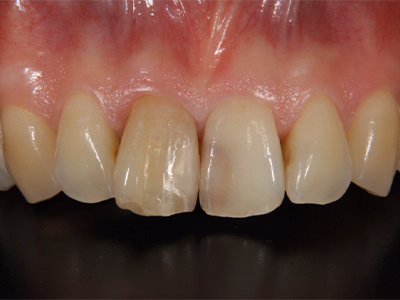

ラミネートべニア

治療前後写真

治療前

治療後

35歳・女性

前歯の審美障害

前歯2本の形態を微量形成→精密印象→仮歯で色・形を確認→後日べニアを強固に接着

治療期間

費用

310,200円(2本)

エナメル質切削に伴う歯髄への影響リスク

接着界面の経年変化

医院コメント

低侵襲で形態・色調を改善。

技工士立会いで色合わせを行い自然感を重視。